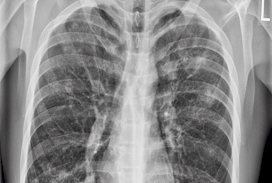

2023 London Imaging Discovery Day